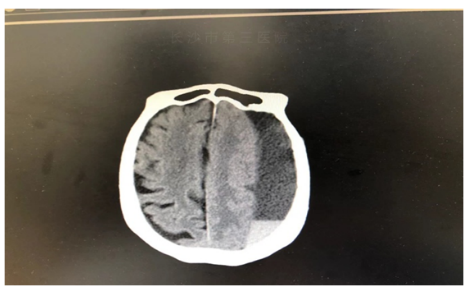

(术前头颅CT)

在长沙市第三医院完善相关检查后,郭娭毑被诊断为左侧额颞顶枕部慢性硬膜下血肿。血肿量约120毫升,若不及时进行手术引流,老人随时可能因脑疝形成导致临床死亡。